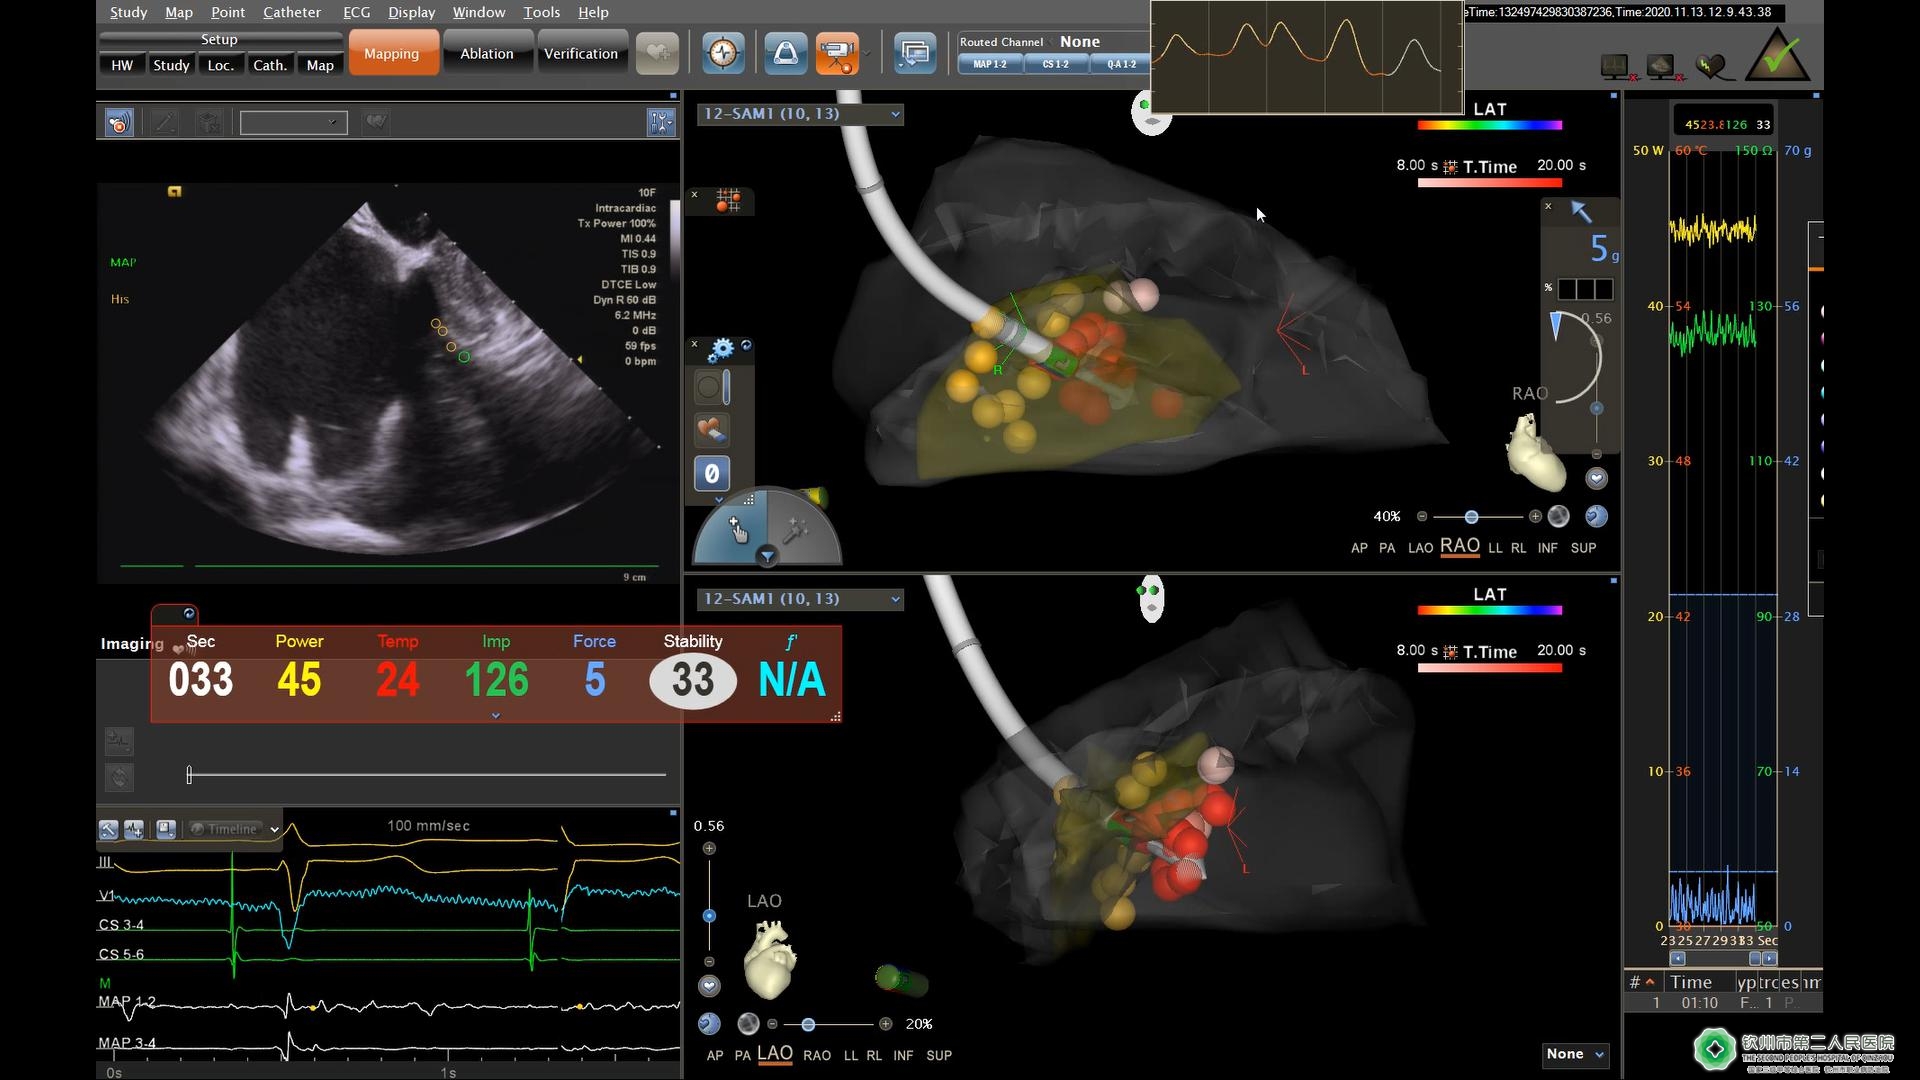

11月13日,钦州市第二人民医院心血管内科心脏电生理介入团队应用三维超声导管指引,成功独立完成了北部湾地区首例导管射频消融室间隔治疗梗阻性肥厚型心肌病手术。目前该手术国内仅有少数几家医院能够开展。

患者黄女士(化名),反复活动后气促、黑朦4年多,平日上3楼或平地行走五百米都存在困难,严重影响生活。到我院就诊后确诊为梗阻性肥厚型心肌病。经药物治疗一段时间,黄女士症状仍不能缓解。既往只能通过外科手术开胸治疗,但手术风险大,创伤大,术后恢复慢。为进一步改善患者生活质量,解除患者病痛,我院心血管内科心电生理介入团队陆永光党委书记、洪泽文副院长、黄军章主任、蓝子深副主任、刘醒存副主任医师等经过反复讨论,并与病人深入沟通,决定采用目前国内、外最先进的治疗办法- ICE(心腔内超声)指导下梗阻性肥厚型心肌病室间隔射频消融术,该技术创伤小、术后恢复快。11月13日,黄女士的手术取得圆满成功,并在“2020全国电生理手术直播季”中现场直播。